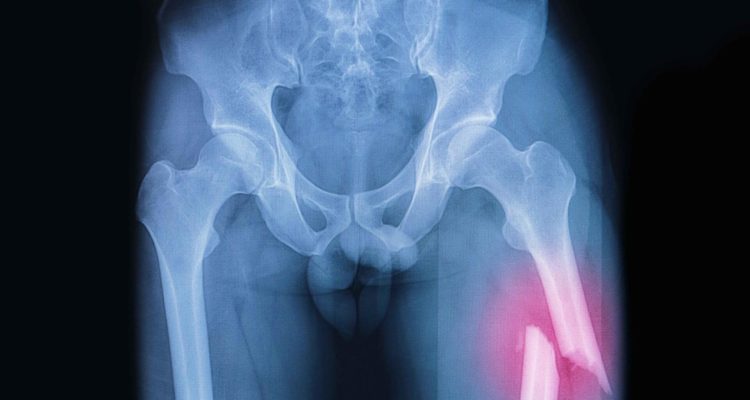

Нове дослідження, в якому взяли участь 5365 літніх чоловіків, показує, що кожен з цих показників пов’язаний з більш високим ризиком розвитку переломів стегна та інших переломів.

Дослідники виявили, що включення обох показників, а не тільки одного, покращує здатність передбачати, у яких чоловіків з найбільшою ймовірністю трапиться перелом стегна або інший перелом в майбутньому.

“І кальциноз черевної аорти, і перелом хребця можна одночасно і швидко виявити на стандартних рентгенограмах або зображеннях щільності латеральної кістки хребта, і це може допомогти в оцінці ризику перелому у літніх чоловіків, у яких є один або обидва фактори ризику”, – розповідає провідний автор доктор Джон Т. Шоусбо з Університету Мінесоти.